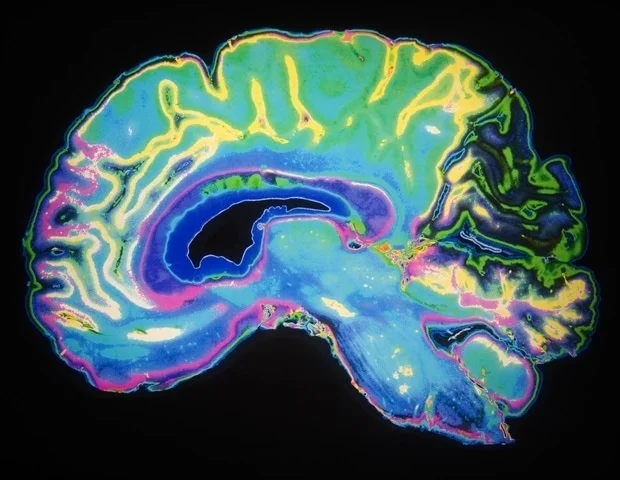

Nowe badanie przeprowadzone przez Karolinska Institutet, opublikowane w Nature Communications, pokazuje, jak rytmiczne fale mózgowe zwane oscylacjami alfa pomagają nam odróżnić nasze własne ciało od świata zewnętrznego. Odkrycia dają nowy wgląd w to, jak mózg integruje sygnały zmysłowe, aby stworzyć spójne poczucie cielesnego „ja”. Co sprawia, że czujesz, że Twoja ręka należy do Ciebie? Może się to wydawać oczywiste, ale zdolność mózgu do odróżnienia siebie od nie-ja jest złożonym procesem. Wykorzystując kombinację eksperymentów behawioralnych, nagrań mózgowych (EEG), stymulacji mózgu i modelowania obliczeniowego, w których wzięło udział łącznie 106 uczestników, naukowcy z Karolinska Institutet zbadali, w jaki sposób mózg łączy sygnały wizualne i dotykowe, aby stworzyć poczucie, że część ciała należy do nas – zjawisko znane jako poczucie własności ciała. Ich eksperymenty wykazały, że częstotliwość fal alfa w korze ciemieniowej – obszarze mózgu przetwarzającym informacje zmysłowe z organizmu – decyduje o tym, jak dokładnie postrzegamy swoje ciało jako własne. Zidentyfikowaliśmy podstawowy proces mózgowy, który kształtuje nasze ciągłe doświadczenie bycia wcielonym. Odkrycie może dostarczyć nowych informacji na temat schorzeń psychiatrycznych, takich jak schizofrenia, w przypadku których zaburzone jest poczucie siebie”. Mariano D’Angelo, główny autor, badacz na Wydziale Neuronauki Instytutu Karolinska. Iluzja gumowej dłoni Uczestnicy wzięli udział w iluzji gumowej dłoni, klasycznej metodzie badania poczucia własności ciała. Kiedy dotknięcie widocznej gumowej dłoni i ukrytej prawdziwej dłoni uczestnika zostały zsynchronizowane, wiele osób zgłosiło poczucie, że gumowa dłoń jest częścią ich ciała. Jednak kiedy nadszedł odpowiedni moment, badanie wykazało, że osoby o szybszych częstotliwościach alfa były bardziej wrażliwe na różnice w czasie między dotykiem widzianym i odczuwanym. Zaobserwowały mniejsze różnice w synchronizacji, tak jakby ich mózgi działały z większą rozdzielczością czasową, co skutkowało bardziej precyzyjnym poczuciem własności ciała. Natomiast wolniejsze częstotliwości alfa były powiązane z szerszym „oknem wiązania czasowego”, powodując, że mózg traktował bardziej asynchroniczne sygnały wizualne i dotykowe tak, jakby występowały razem osłabiające rozróżnienie między ciałem a światem Lepsze protezy i doświadczenia VR Aby sprawdzić, czy częstotliwość alfa bezpośrednio powoduje te efekty percepcyjne, badacze wykorzystali nieinwazyjną elektryczną stymulację mózgu, aby nieznacznie przyspieszyć lub spowolnić fale alfa uczestników. Wyniki pokazały, że dostosowanie częstotliwości alfa w ten sposób zmieniło również dokładność, z jaką ludzie odczuwali własność ciała i jak dokładnie postrzegali bodźce wzrokowe i dotykowe jako jednoczesne. Modele obliczeniowe wykazały, że częstotliwość alfa wpływa na to, jak precyzyjnie mózg ocenia czas sygnałów sensorycznych te fale mózgowe regulują czasową precyzję percepcji, a tym samym pomagają kształtować poczucie cielesnego „ja” „Nasze odkrycia pomagają wyjaśnić, w jaki sposób mózg radzi sobie z wyzwaniem integracji sygnałów z ciała w celu stworzenia spójnego poczucia siebie” – mówi Henrik Ehrsson, profesor na Wydziale Neuronauki Karolinska Institutet i ostatni autor badania. „Może to przyczynić się do opracowania lepszych protez kończyn i bardziej realistycznych doświadczeń w wirtualnej rzeczywistości”. Uniwersytet Aix-Marseille we Francji, finansowany przez Europejską Radę ds. Badań Naukowych (ERC), Szwedzką Radę ds. Badań, VINNOVA, StratNeuro i A*Midex. Źródło: Referencje w czasopiśmie: D’Angelo, M. i in. (2026). Częstotliwość alfa ciemieniowa kształtuje percepcję własnego ciała poprzez modulację czasowej integracji sygnałów cielesnych. 10.1038/s41467-025-67657-w https://www.nature.com/articles/s41467-025-67657-w